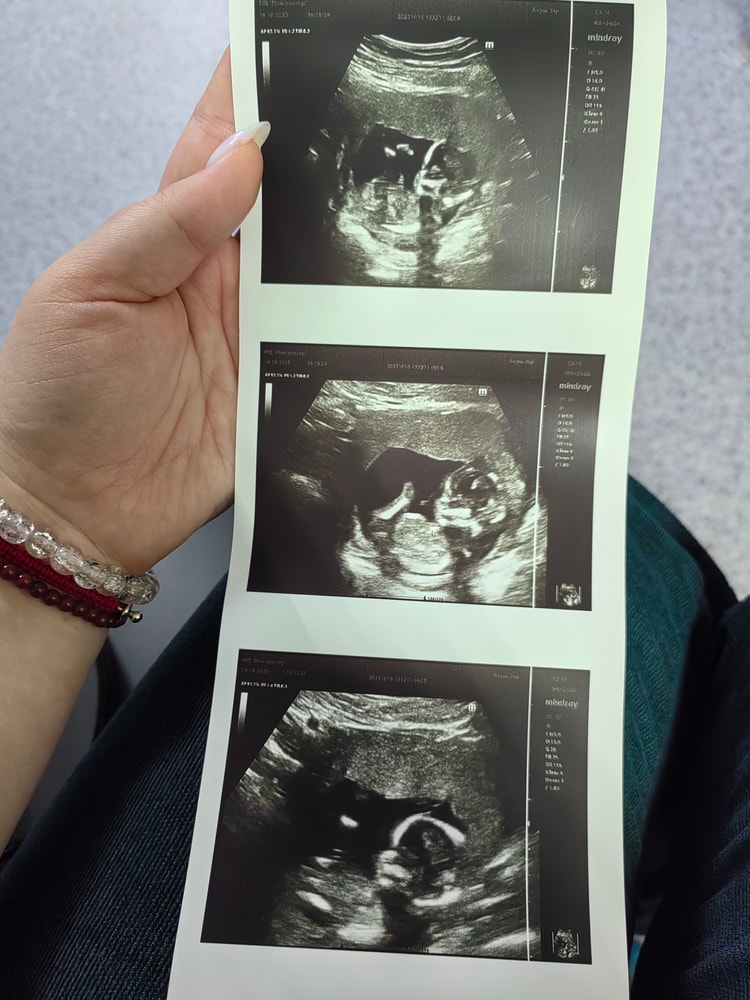

Узи 15 неделек

Сходила на узи в 15 недель (по скринингу) на этом узи написали в заключении беременность 15н3д. Очень интересно 🤔

В общем, все хорошо. Малыш растёт как положено, все срокам соответствует. Мальчишку подтвердили, все вывалил на показ 😄

По узи особой активности от него не вижу, лежит немного ногами дёргает. Весь в мать 🤣

Слава Богу шейка не укорачивается, а то по скринингу 31 намерили, по узи в этот раз 33, облегчение.